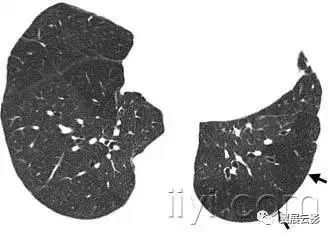

四十一、nodular pattern 粟粒样结节影

本名词尚未明确如何翻译好

平片和CT:粟粒样结节影表现为胸片上无数的小圆形结节,分布弥漫,指教解郁2~10mm内(图)。病变分布广泛但是不一定均匀,在CT上具有三种解剖分布模式:小叶中心性、沿淋巴管或者随机。